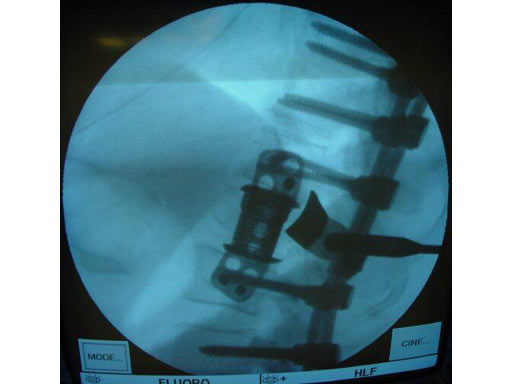

Case 1

Pathology: 68 - year- old male sustained a high energy C-type shear fracture of the L1 vertebra after a fall off of a bridge. The patient had received posterior fixation three weeks before this accident, but still displayed intractable leg pain. The posterior fixation consisted of Dual - Opening USS pedicle screws at T10 -T12 and L2- L3. The preoperative x- rays and MRI showed that the patient had some slippage at the L1- L2 disc and that there were still several pieces of bone impinging on the spinal canal.

Indication: Corpectomy of the L1 vertebral body.